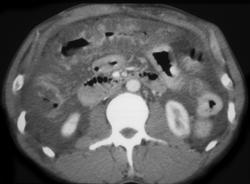

Appendicitis